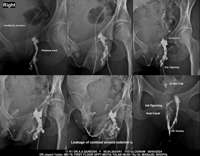

Section: FISTULOGRAM Total: 8 images

BaM Enteroclysis Loopogram BaE Fistulogram Urethrogram HSG